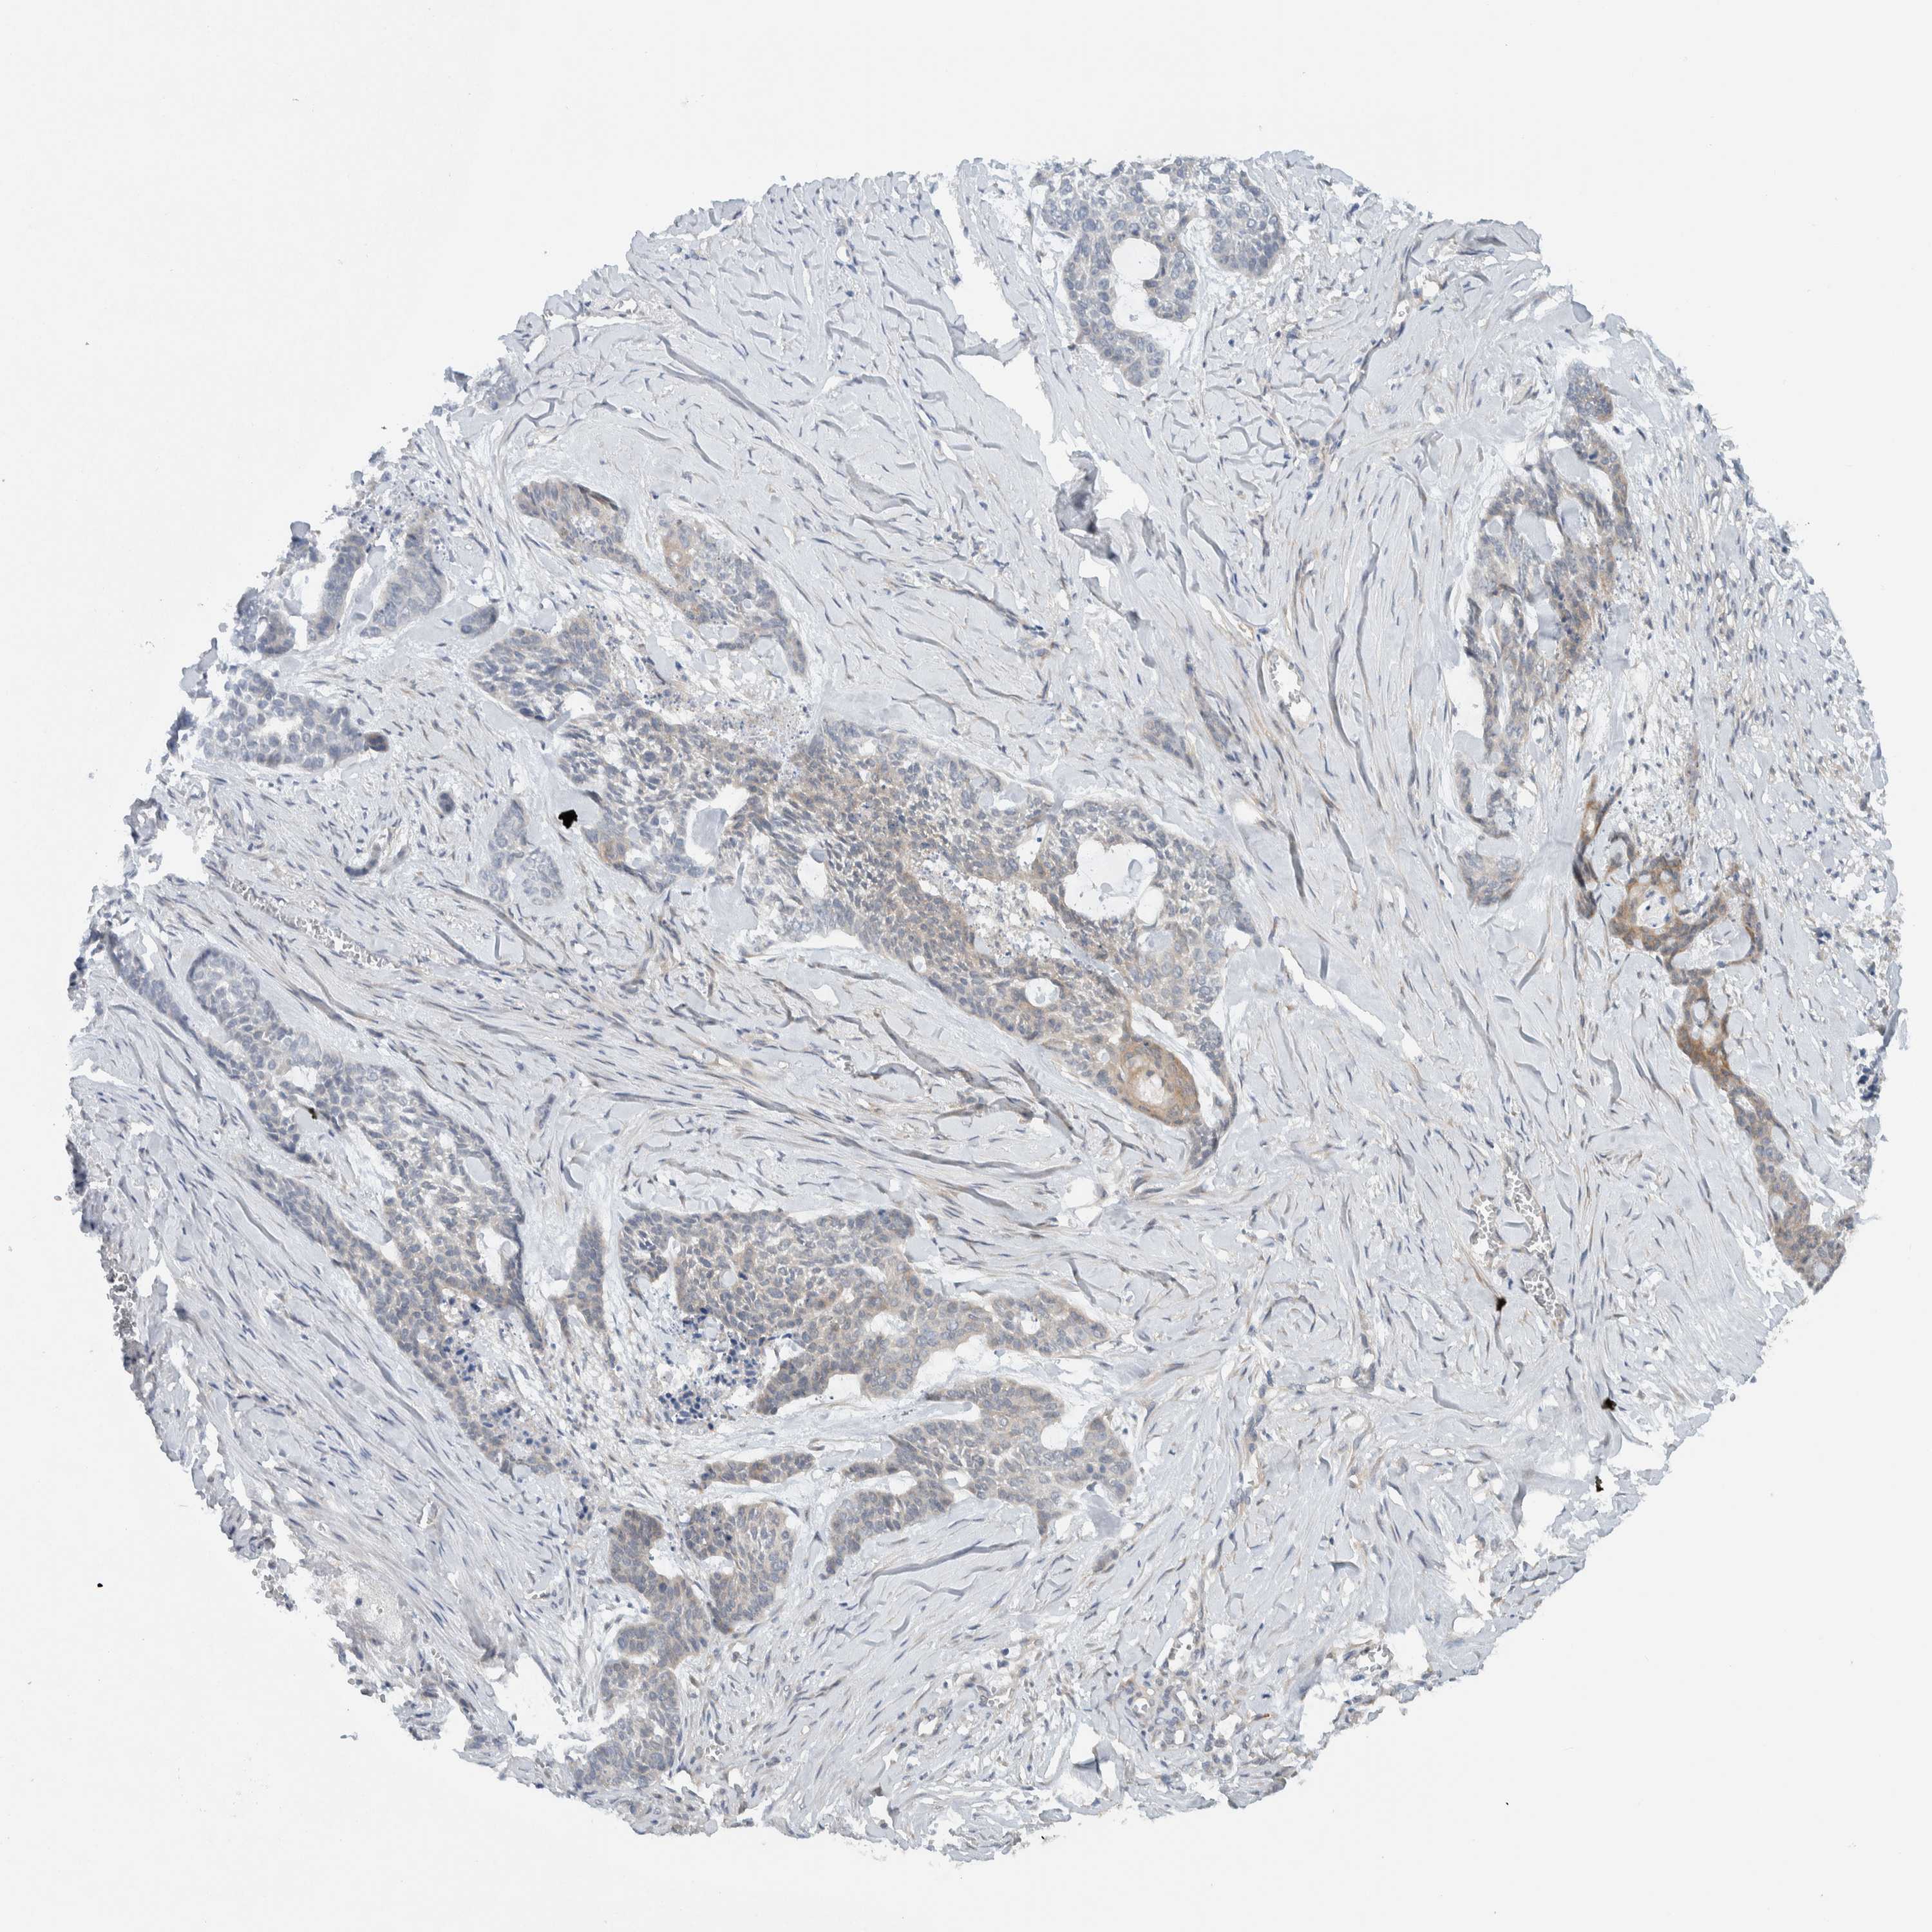

Basal cell and squamous cell cancer

SKIN CANCER - Protein expressioni

A mouse-over function shows sample information and annotation data. Click on an image to view it in a full screen mode. Samples can be filtered based on level of antibody staining by selecting one or several of the following categories: high, medium, low and not detected. The assay and annotation is described here.

Antibody stainingi

Antibody staining in the annotated cell types in the current human tissue is reported as not detected, low, medium, or high, based on conventional immunohistochemistry profiling in selected tissues. This score is based on the combination of the staining intensity and fraction of stained cells.

Each image is clickable and will lead to virtual microscopy that enables deeper exploration of all samples and also displays staining intensity scores, fraction scores and subcellular localization as well as patient and tissue information for each sample.

Antibody HPA024093

Staining

High

Medium

Low

Not detected

Intensity

Strong

Moderate

Weak

Negative

Quantity

>75%

75%-25%

<25%

None

Location

Nuclear

Cytoplasmic/membranous

Cytoplasmic/membranous,nuclear

Basal cell carcinoma